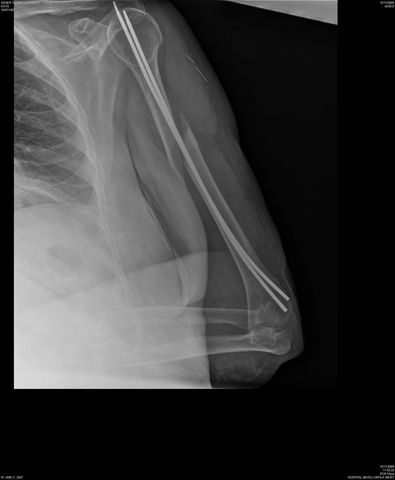

Fractura de húmero tras osteosíntesis con clavo gamma.